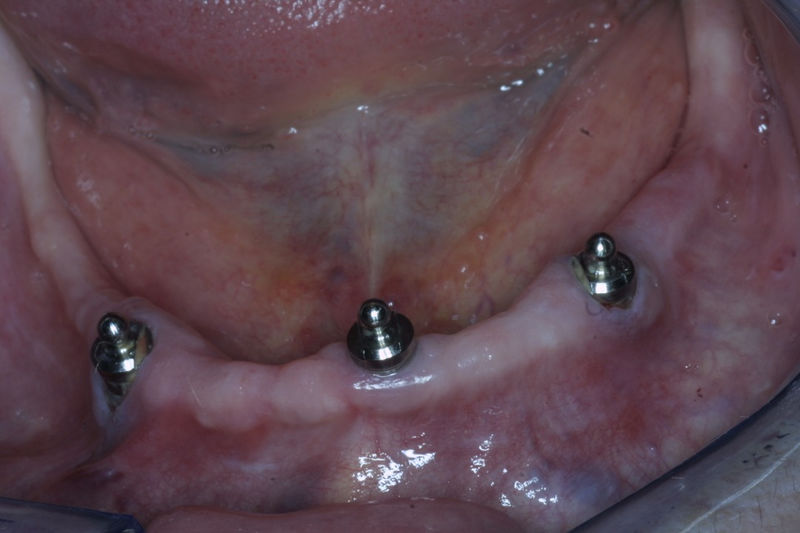

Restauraciones fabricadas en el laboratorio los cuales se usan para reemplazar dientes ausentes en toda una arcada usando implantes y/o tejidos blandos como soporte y que pueden y deben de ser removidas para su limpieza. Para poder enviar el caso al laboratorio se toman impresiones utilizando materiales de impresión o técnicas modernas digitales.

Son estructuras de titanio las cuales se colocan en el hueso y se utilizan para soportar coronas, prótesis fijas, removibles y totales. La colocación de los implantes se hacen previo análisis tomográfico.